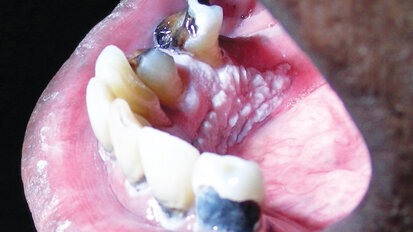

Complete reconstruction for a patient with chronic tooth decay

When oral health is neglected for extensive periods of time, dental conditions like tooth decay and periodontal disease can advance to a point that, prior ...